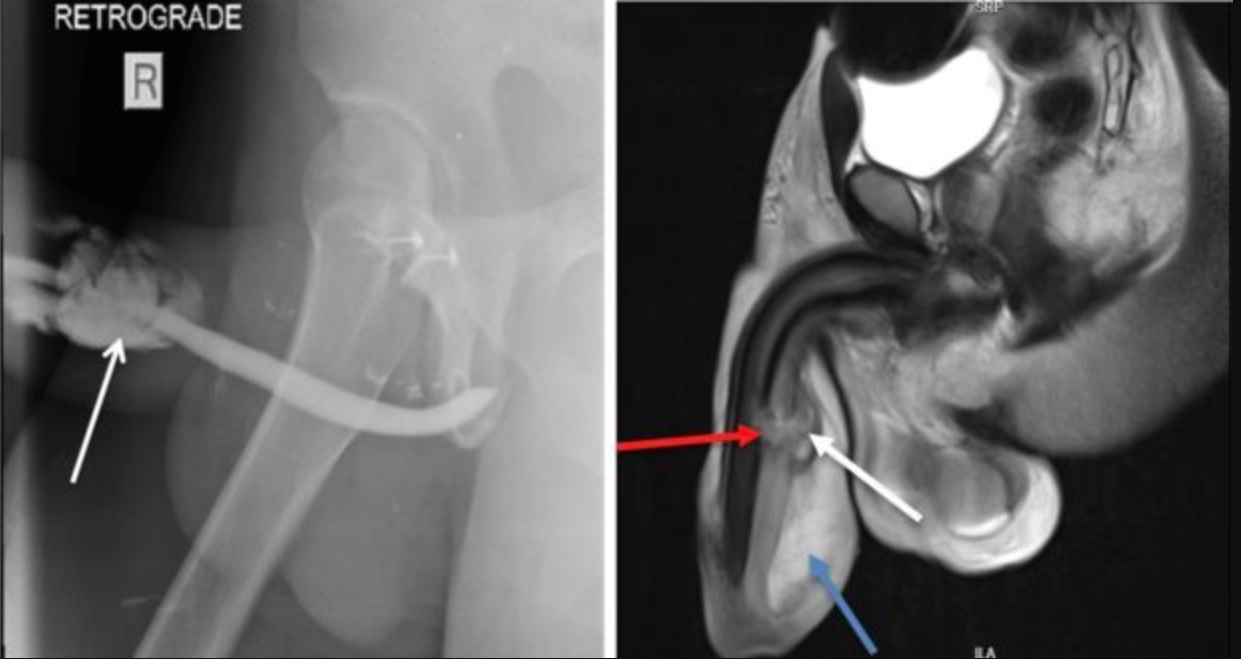

O homem contou aos profissionais que a namorada estava por cima dele durante o sexo, quando ele ouviu um estalo após o pênis escorregar e atingir o períneo da mulher. A lesão causou perda da ereção, sangue pela uretra e inchaço.